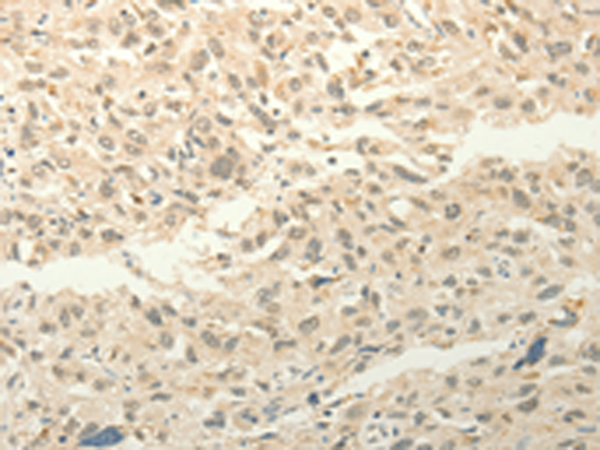

IHC positive control: |

Human lung cancer and Human ovarian cancer |

IHC Recommend dilution: |

50-200 |